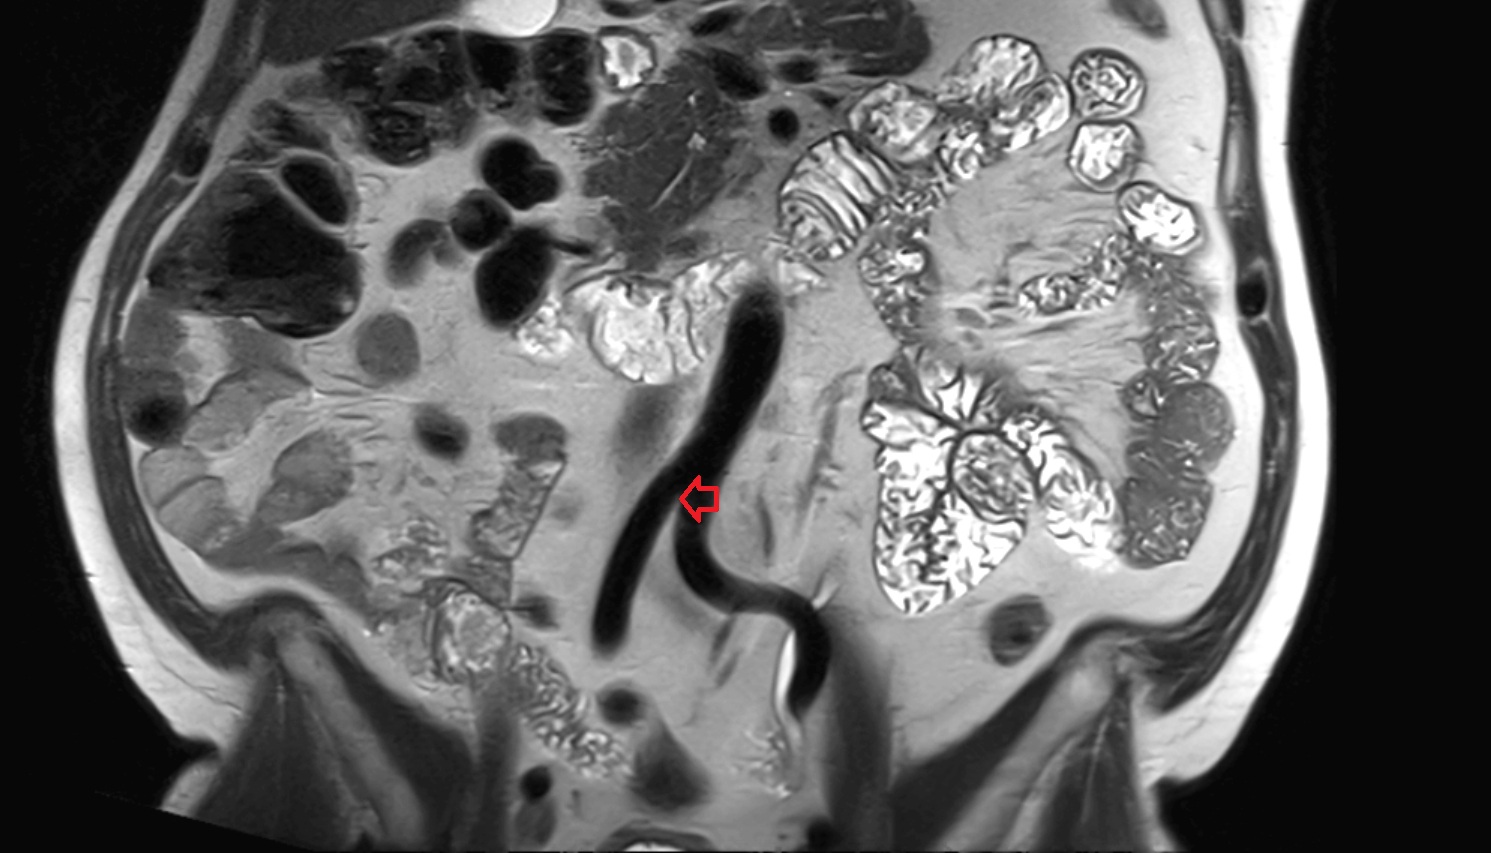

- Uterus

- Body of uterus

- Fundus of uterus

- Cervix of uterus

- Isthmus of uterus

- Vagina

- Fornix of the vagina

- Endometrium of uterus

- Myometrium of uterus

- Perimetrium of uterus

- Junctional zone of uterus